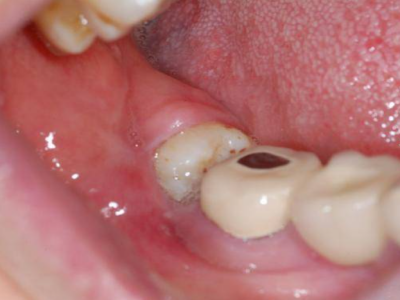

智齿冠周炎右下方的牙龈最内侧红肿图

智齿冠周炎患者右下方的牙龈最内侧有红肿,红肿处有一小创口,可见其内的牙齿,牙齿未完整露出,小创口边缘微微发白,患者自觉有明显疼痛。